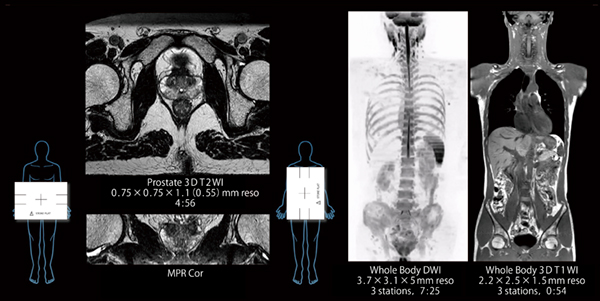

新井:欧米でレビューした際に,欧米人の体格でも巻き付けられることが側面の感度を保つ上で重要であるというご意見をいただき,現在のような大きさになりました。また,開発当初から縦置き,横置きが可能なコイルを想定していました。縦置きにして使用することで,日本人の体格に対しては,頭頸部用コイル,腹部用コイル,Spineコイルの3つの標準コイルで頭部~骨盤までの広範囲をカバーすることが可能になります(図2)。

(1) 縦置きにすることで体幹部の広い範囲をカバーできる

(2) 軽量で柔らかい素材で作られており,巻きつけるようにセッティング可能

図2 腹部用受信コイルの横置き,縦置きの使用例